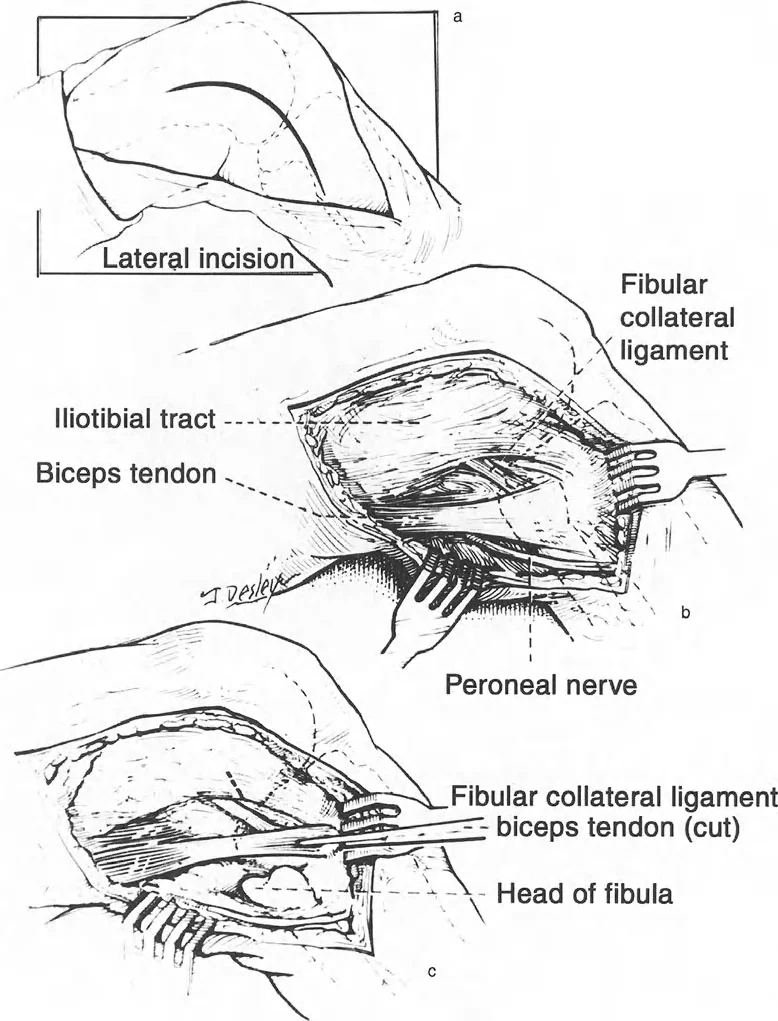

مساهمات باولز وماكيت (Pauwels and Maquet): رواد الميكانيكا الحيوية

كان فريدريش باولز (Friedrich Pauwels) في الثمانينيات من أوائل الجراحين الذين أدركوا الأهمية العميقة للميكانيكا الحيوية وعلاقتها المباشرة بالتخطيط الجراحي لتصحيح التشوه عبر قطع العظم. لقد أ